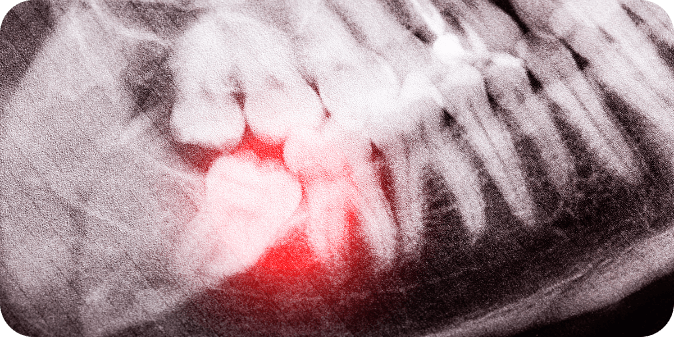

Wisdom Teeth

Wisdom teeth are molars that grow at the back of the mouth, and sometimes, these can cause pain, swelling, and other complications when they don’t have enough space to grow. Extracting these teeth is a straightforward way to alleviate these symptoms.